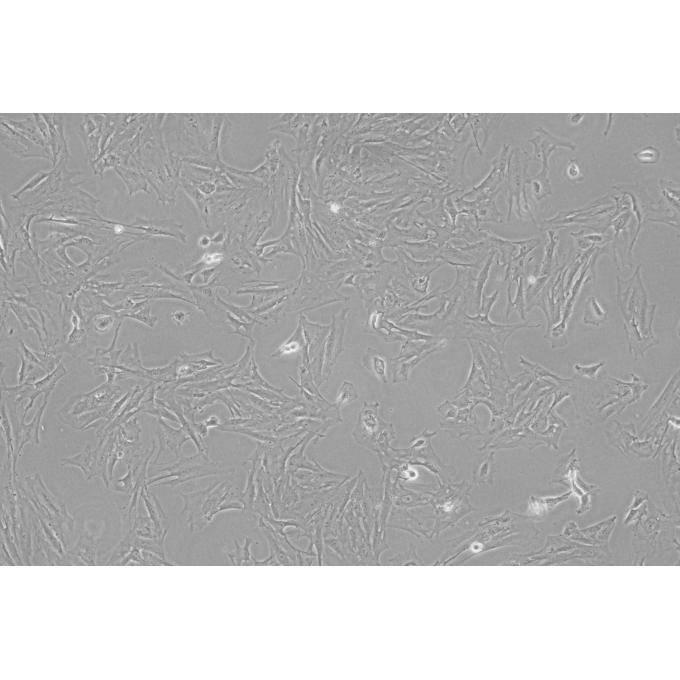

• 名称:U0126-EtOH

• 简介:U0126-EtOH is an inhibitor of both MEK1 and MEK2 with an IC50 of 72 nM and 58 nM respectively.

• 应用:MEK inhibitor

• 作用机制:Inhibitor